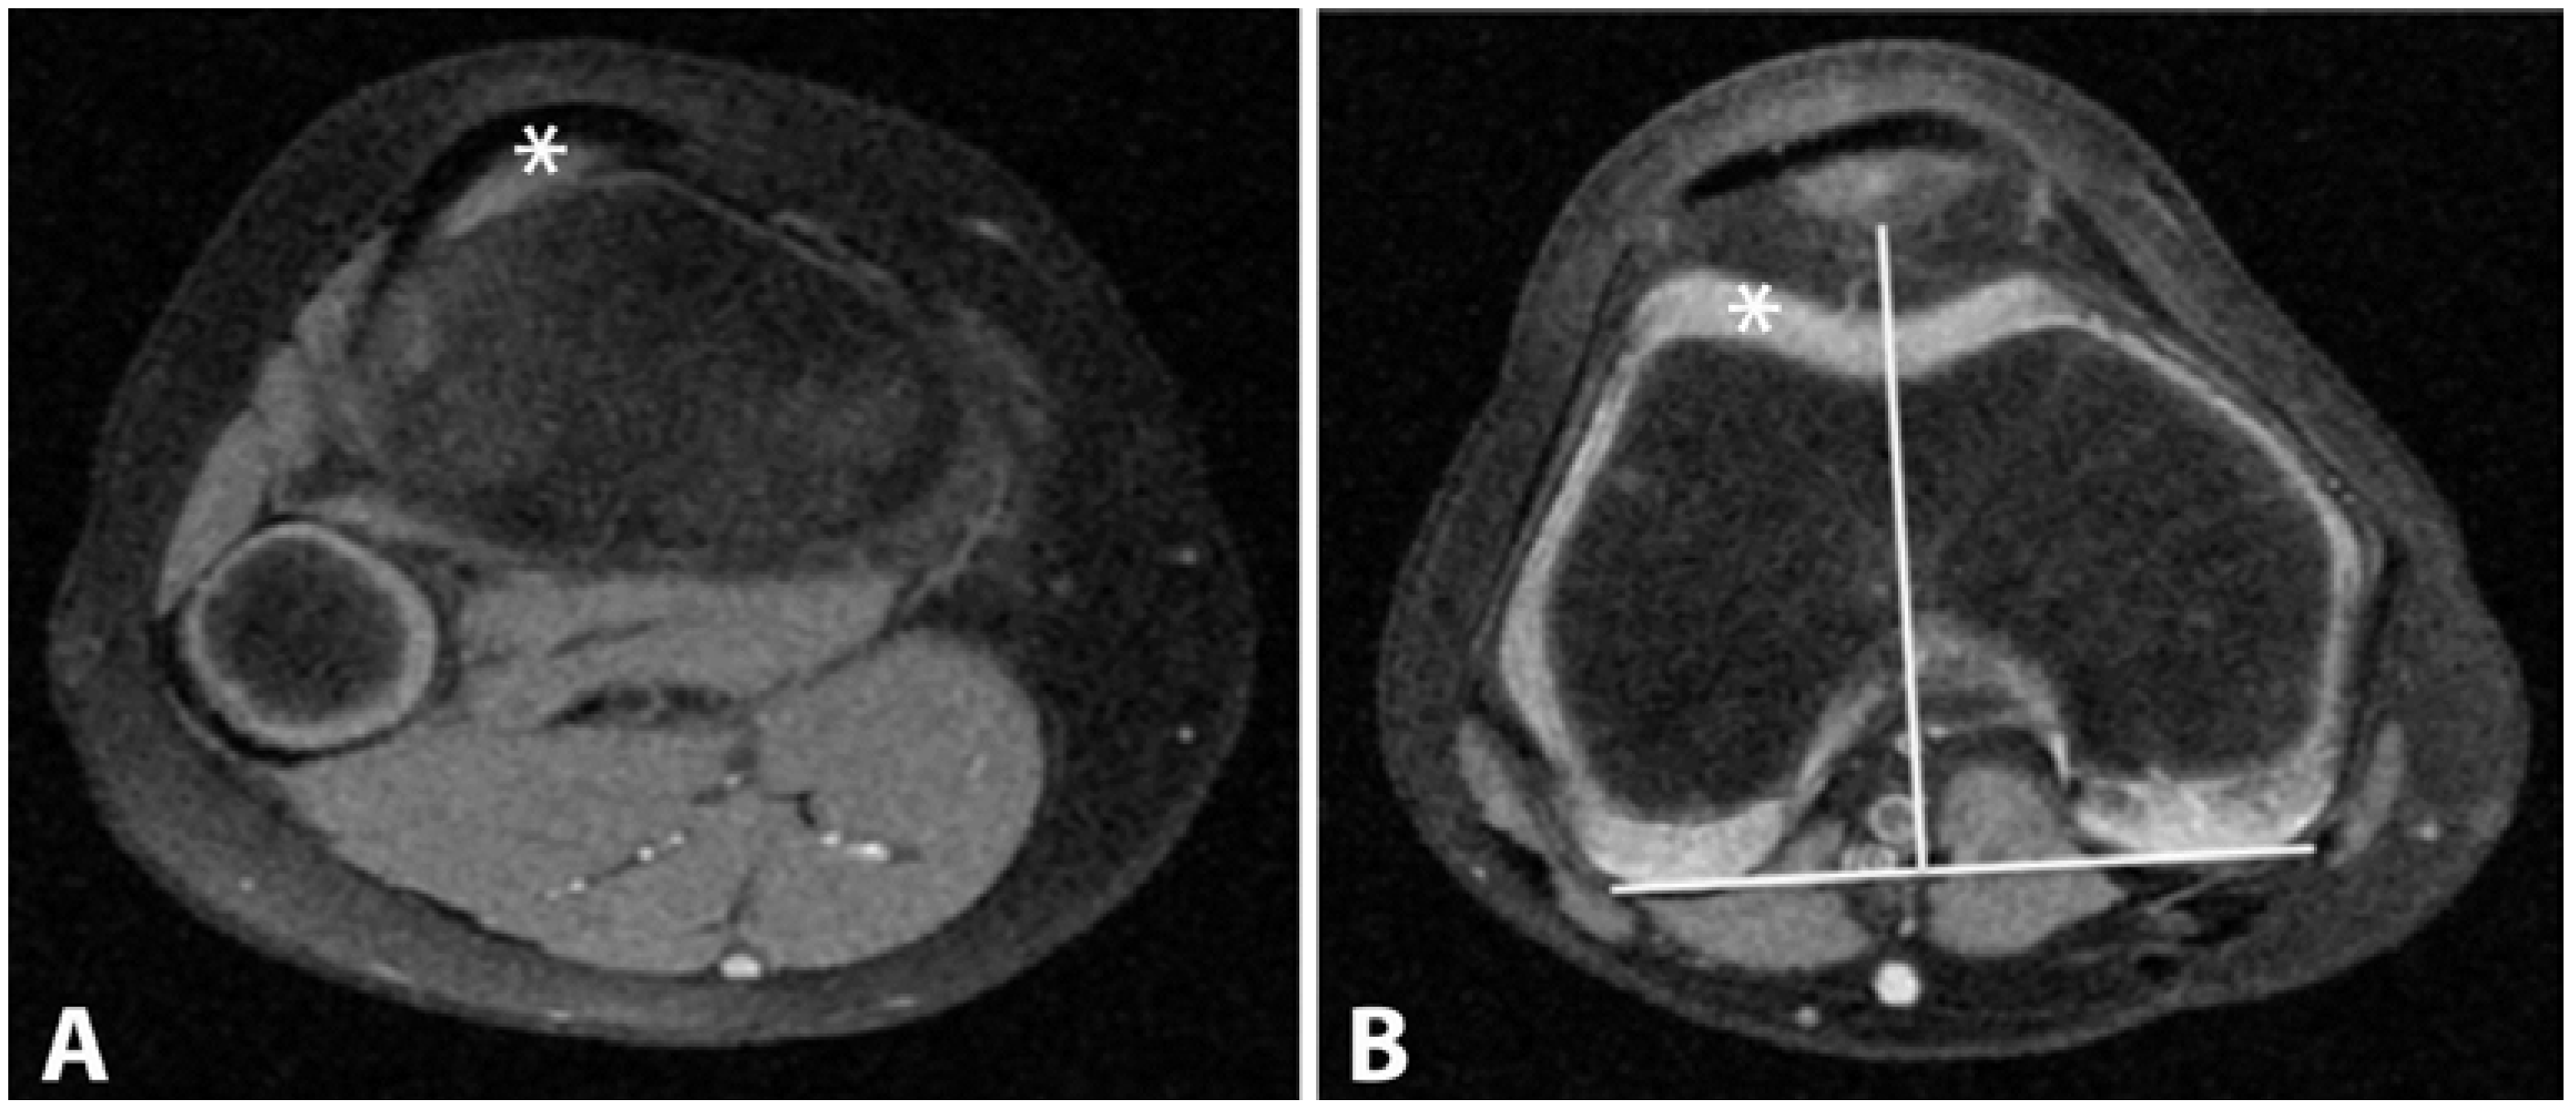

Figure 4.

(A) and (B): Tibial Tuberosity–Trochlear Groove (TT–TG) distance. The superior attachment of the patellar tendon at the tibial tuberosity is marked (A); and then transposed on our standard axial sequence (B). The distance between the marker (*) and solid white line that is extending through the deep sulcus to the reference line was recorded.